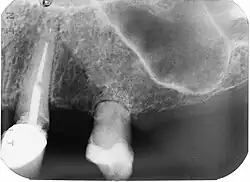

Reabsorción de reemplazo externo

Ocurre después de la anquilosis de la raíz del hueso alveolar. El tejido dental se reabsorbe y se reemplaza con hueso. Este proceso no es muy entendido.

Se piensa que después de la unión de hueso y diente y la destrucción del ligamento periodontal, los reguladores protectores liberados por el ligamento periodontal para proteger a la raíz de la resorción ya no se encuentran. Esto hace que el tejido dental sea reabsorbido por los osteoclastos y reemplazado por hueso como si fuera parte del proceso homeostático continuo de recambio óseo.